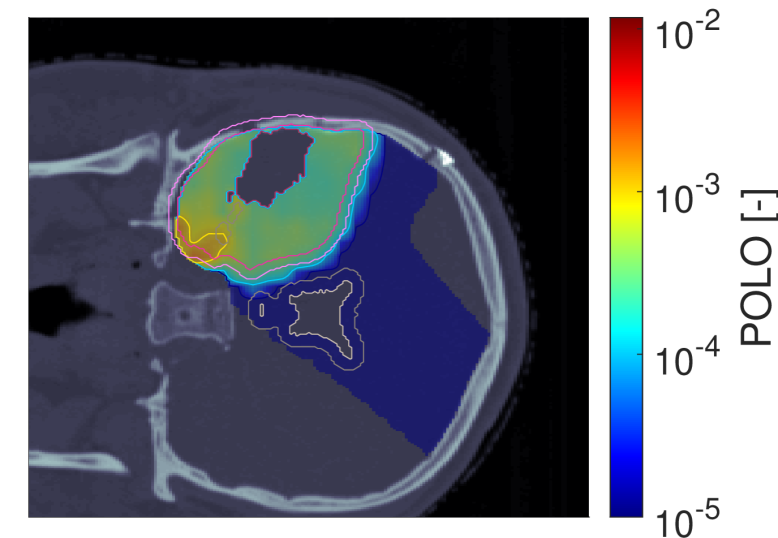

Figure 2 shows the optimal slice images of the dose (left), dose-averaged LET (middle) and POLO distribution (right). On the underlying CT scan, the tumor volumes are marked by violet to purple contours, while the VS (ventricles and 4 mm4\text{\,}\mathrm{mm} fringe) is outlined in white and gray. We observe the high-dose region covering all of the GTV, with a largely homogeneous transition to the clinical and planning target volumes (CTV, PTV), and a moderate to severe overlap to the VS. The dose-averaged LET distributes in layers, with increased values around the contour edge of CTV/PTV and local peaks at the distal ends of the proton beams. Accordingly, hot spots on the POLO map are found in regions where dose and dose-averaged LET scale up, or close to the VS. Beyond the PTV, the POLO map reveals cold spots, due to the steepness of the dose and dose-averaged LET gradients.

dRBE,fxd_{RBE,fx}ABCD ldl_{d}ABCD ppABCD

Refer to caption Refer to caption Refer to caption

NTCP:45.59 %NTCP:$45.59\text{\,}\mathrm{\char 37\relax}$ABCD

Figure 2: Optimal 2D slice images of the RBE-weighted fractional dose dRBE,fxd_{RBE,fx}, the dose-averaged linear energy transfer ldl_{d} and the probability function values pip_{i} for the baseline plan. The dose distribution (left) shows high target coverage with decreasing exposure beyond the CTV/PTV margins, but also visibly overlaps with parts of the VS. Meanwhile, for the dose-averaged LET (middle), layered homogeneity in the target volumes and local maxima at the distal ends of the proton beams can be observed. This results in more pronounced levels of POLO values within the target volumes, particularly in the presence of local dose-averaged LET maxima and in the environment of the VS. Referring back to the POLO model from Equation 1 and (3), we can expect exactly this type of coherence between the model output, the physical input feature profiles and the increased local risk near the VS. The baseline treatment plan exhibits a complication risk of 45.59 %45.59\text{\,}\mathrm{\char 37\relax} after evaluation of the POLO distribution with NTCPpNTCP_{p}.